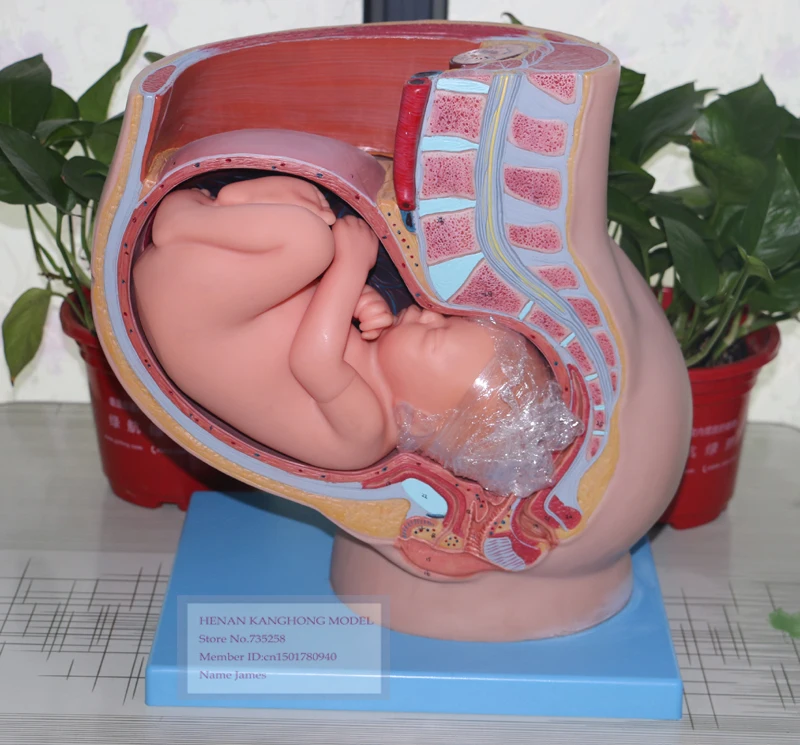

Моменты волшебства: Рождение ребенка в животе мамы

Раздел: Фотозарисовки